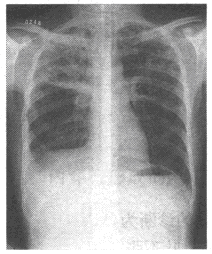

63、单项选择题

男,28岁,轻咳2个月,有盗汗。胸片如图

A.Ⅰ

B.Ⅱ

C.Ⅲ

D.Ⅳ

E.Ⅵ